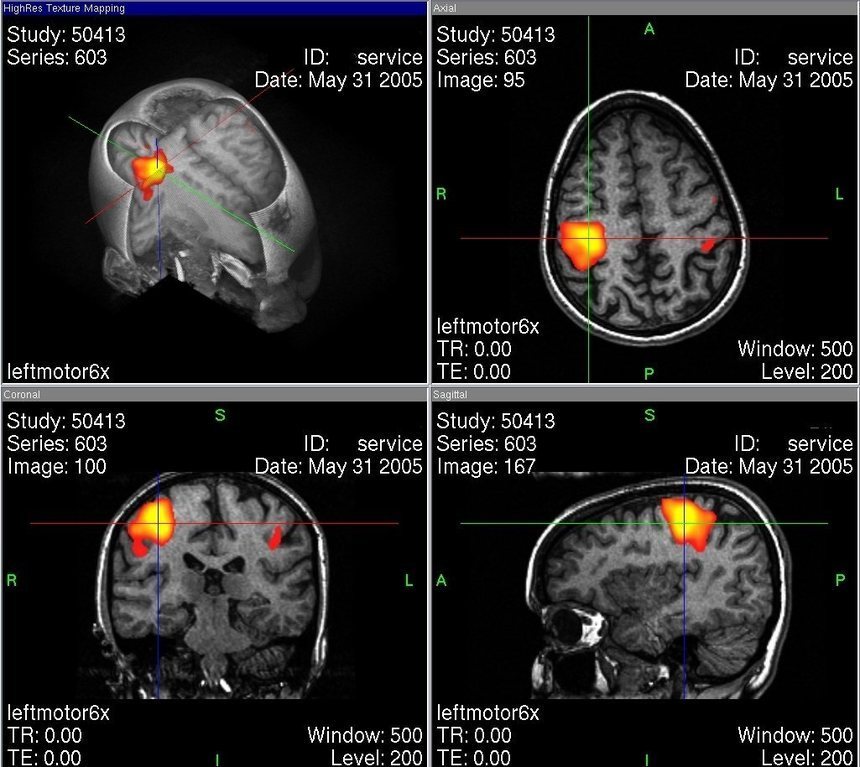

En un artículo de la revista Plos One, se explica que los participantes fueron sometidos a escáneres de resonancia magnética funcional (fMRI), un procedimiento clínico y de investigación que permite mostrar en imágenes las regiones cerebrales que ejecutan una tarea determinada, tanto al inicio del experimento como ocho meses después del inicio de la psicoterapia.

En ambos momentos, a todos ellos se les presentaron estímulos experimentales en forma de frases que describían sus patrones disfuncionales en sus relaciones interpersonales, con el fin de ver cómo reaccionaban sus cerebros a dichos estímulos (por ejemplo, se les dijo: “usted desea ser aceptado por los demás, por lo que hace demasiado por ellos”).

En el primer escáner, se constató que ciertas regiones del cerebro de los individuos con trastorno depresivo reaccionaban a las frases presentadas con hiperactividad.

Sin embargo, ocho meses después de iniciada la terapia psicodinámica, los cerebros de los pacientes con depresión habían cambiado: su actividad ya no se distinguía de la de los participantes sanos. Por otra parte, las evaluaciones sobre sus síntomas depresivos mejoraron significativamente tras esos ocho meses.

Según Taubner, el estudio constata, por tanto, que los cambios en el sistema límbico desencadenados por estímulos con un contenido clínicamente relevante pueden ser normalizados con un tratamiento psicológico.